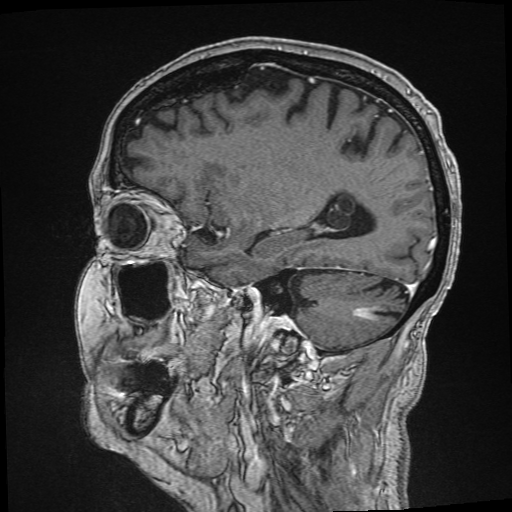

Refer to captionRefer to caption𝐱PCsubscript𝐱PC\mathbf{x}_{\mathrm{PC}}bold_x start_POSTSUBSCRIPT roman_PC end_POSTSUBSCRIPTRefer to captionRefer to caption𝐱LDsubscript𝐱LD\mathbf{x}_{\mathrm{LD}}bold_x start_POSTSUBSCRIPT roman_LD end_POSTSUBSCRIPTRefer to captionRefer to caption𝐱SDsubscript𝐱SD\mathbf{x}_{\mathrm{SD}}bold_x start_POSTSUBSCRIPT roman_SD end_POSTSUBSCRIPTRefer to captionRefer to captionAm-3D [14]Refer to captionRefer to captionPa-2.5D [8]Refer to captionRefer to caption𝐱~SDsubscript~𝐱SD\tilde{\mathbf{x}}_{\mathrm{SD}}over~ start_ARG bold_x end_ARG start_POSTSUBSCRIPT roman_SD end_POSTSUBSCRIPT (ours)ptPhilips Achieva 3TGadobutrol dLD=0.10subscript𝑑LD0.10d_{\mathrm{LD}}=0.10italic_d start_POSTSUBSCRIPT roman_LD end_POSTSUBSCRIPT = 0.10ptPhilips Ingenia 1.5TGadoterate dLD=0.33subscript𝑑LD0.33d_{\mathrm{LD}}=0.33italic_d start_POSTSUBSCRIPT roman_LD end_POSTSUBSCRIPT = 0.33Refer to captionRefer to caption𝐱PCsubscript𝐱PC\mathbf{x}_{\mathrm{PC}}bold_x start_POSTSUBSCRIPT roman_PC end_POSTSUBSCRIPTRefer to captionRefer to caption𝐱LDsubscript𝐱LD\mathbf{x}_{\mathrm{LD}}bold_x start_POSTSUBSCRIPT roman_LD end_POSTSUBSCRIPTRefer to captionRefer to caption𝐱SDsubscript𝐱SD\mathbf{x}_{\mathrm{SD}}bold_x start_POSTSUBSCRIPT roman_SD end_POSTSUBSCRIPTRefer to captionRefer to captionAm-3D [14]Refer to captionRefer to captionPa-2.5D [8]Refer to captionRefer to caption𝐱~SDsubscript~𝐱SD\tilde{\mathbf{x}}_{\mathrm{SD}}over~ start_ARG bold_x end_ARG start_POSTSUBSCRIPT roman_SD end_POSTSUBSCRIPT (ours)ptPhilips Achieva 3TGadobutrol dLD=0.10subscript𝑑LD0.10d_{\mathrm{LD}}=0.10italic_d start_POSTSUBSCRIPT roman_LD end_POSTSUBSCRIPT = 0.10ptPhilips Ingenia 1.5TGadoterate dLD=0.33subscript𝑑LD0.33d_{\mathrm{LD}}=0.33italic_d start_POSTSUBSCRIPT roman_LD end_POSTSUBSCRIPT = 0.33Refer to captionRefer to caption𝐱PCsubscript𝐱PC\mathbf{x}_{\mathrm{PC}}bold_x start_POSTSUBSCRIPT roman_PC end_POSTSUBSCRIPTRefer to captionRefer to caption𝐱LDsubscript𝐱LD\mathbf{x}_{\mathrm{LD}}bold_x start_POSTSUBSCRIPT roman_LD end_POSTSUBSCRIPTRefer to captionRefer to caption𝐱SDsubscript𝐱SD\mathbf{x}_{\mathrm{SD}}bold_x start_POSTSUBSCRIPT roman_SD end_POSTSUBSCRIPTRefer to captionRefer to captionAm-3D [14]Refer to captionRefer to captionPa-2.5D [8]Refer to captionRefer to caption𝐱~SDsubscript~𝐱SD\tilde{\mathbf{x}}_{\mathrm{SD}}over~ start_ARG bold_x end_ARG start_POSTSUBSCRIPT roman_SD end_POSTSUBSCRIPT (ours)ptPhilips Achieva 3TGadobutrol dLD=0.10subscript𝑑LD0.10d_{\mathrm{LD}}=0.10italic_d start_POSTSUBSCRIPT roman_LD end_POSTSUBSCRIPT = 0.10ptPhilips Ingenia 1.5TGadoterate dLD=0.33subscript𝑑LD0.33d_{\mathrm{LD}}=0.33italic_d start_POSTSUBSCRIPT roman_LD end_POSTSUBSCRIPT = 0.33Refer to captionRefer to caption𝐱PCsubscript𝐱PC\mathbf{x}_{\mathrm{PC}}bold_x start_POSTSUBSCRIPT roman_PC end_POSTSUBSCRIPTRefer to captionRefer to caption𝐱LDsubscript𝐱LD\mathbf{x}_{\mathrm{LD}}bold_x start_POSTSUBSCRIPT roman_LD end_POSTSUBSCRIPTRefer to captionRefer to caption𝐱SDsubscript𝐱SD\mathbf{x}_{\mathrm{SD}}bold_x start_POSTSUBSCRIPT roman_SD end_POSTSUBSCRIPTRefer to captionRefer to captionAm-3D [14]Refer to captionRefer to captionPa-2.5D [8]Refer to captionRefer to caption𝐱~SDsubscript~𝐱SD\tilde{\mathbf{x}}_{\mathrm{SD}}over~ start_ARG bold_x end_ARG start_POSTSUBSCRIPT roman_SD end_POSTSUBSCRIPT (ours)ptPhilips Achieva 3TGadobutrol dLD=0.10subscript𝑑LD0.10d_{\mathrm{LD}}=0.10italic_d start_POSTSUBSCRIPT roman_LD end_POSTSUBSCRIPT = 0.10ptPhilips Ingenia 1.5TGadoterate dLD=0.33subscript𝑑LD0.33d_{\mathrm{LD}}=0.33italic_d start_POSTSUBSCRIPT roman_LD end_POSTSUBSCRIPT = 0.33Refer to captionRefer to caption𝐱PCsubscript𝐱PC\mathbf{x}_{\mathrm{PC}}bold_x start_POSTSUBSCRIPT roman_PC end_POSTSUBSCRIPTRefer to captionRefer to caption𝐱LDsubscript𝐱LD\mathbf{x}_{\mathrm{LD}}bold_x start_POSTSUBSCRIPT roman_LD end_POSTSUBSCRIPTRefer to captionRefer to caption𝐱SDsubscript𝐱SD\mathbf{x}_{\mathrm{SD}}bold_x start_POSTSUBSCRIPT roman_SD end_POSTSUBSCRIPTRefer to captionRefer to captionAm-3D [14]Refer to captionRefer to captionPa-2.5D [8]Refer to captionRefer to caption𝐱~SDsubscript~𝐱SD\tilde{\mathbf{x}}_{\mathrm{SD}}over~ start_ARG bold_x end_ARG start_POSTSUBSCRIPT roman_SD end_POSTSUBSCRIPT (ours)ptPhilips Achieva 3TGadobutrol dLD=0.10subscript𝑑LD0.10d_{\mathrm{LD}}=0.10italic_d start_POSTSUBSCRIPT roman_LD end_POSTSUBSCRIPT = 0.10ptPhilips Ingenia 1.5TGadoterate dLD=0.33subscript𝑑LD0.33d_{\mathrm{LD}}=0.33italic_d start_POSTSUBSCRIPT roman_LD end_POSTSUBSCRIPT = 0.33Refer to captionRefer to caption𝐱PCsubscript𝐱PC\mathbf{x}_{\mathrm{PC}}bold_x start_POSTSUBSCRIPT roman_PC end_POSTSUBSCRIPTRefer to captionRefer to caption𝐱LDsubscript𝐱LD\mathbf{x}_{\mathrm{LD}}bold_x start_POSTSUBSCRIPT roman_LD end_POSTSUBSCRIPTRefer to captionRefer to caption𝐱SDsubscript𝐱SD\mathbf{x}_{\mathrm{SD}}bold_x start_POSTSUBSCRIPT roman_SD end_POSTSUBSCRIPTRefer to captionRefer to captionAm-3D [14]Refer to captionRefer to captionPa-2.5D [8]Refer to captionRefer to caption𝐱~SDsubscript~𝐱SD\tilde{\mathbf{x}}_{\mathrm{SD}}over~ start_ARG bold_x end_ARG start_POSTSUBSCRIPT roman_SD end_POSTSUBSCRIPT (ours)ptPhilips Achieva 3TGadobutrol dLD=0.10subscript𝑑LD0.10d_{\mathrm{LD}}=0.10italic_d start_POSTSUBSCRIPT roman_LD end_POSTSUBSCRIPT = 0.10ptPhilips Ingenia 1.5TGadoterate dLD=0.33subscript𝑑LD0.33d_{\mathrm{LD}}=0.33italic_d start_POSTSUBSCRIPT roman_LD end_POSTSUBSCRIPT = 0.33Refer to captionRefer to caption𝐱PCsubscript𝐱PC\mathbf{x}_{\mathrm{PC}}bold_x start_POSTSUBSCRIPT roman_PC end_POSTSUBSCRIPTRefer to captionRefer to caption𝐱LDsubscript𝐱LD\mathbf{x}_{\mathrm{LD}}bold_x start_POSTSUBSCRIPT roman_LD end_POSTSUBSCRIPTRefer to captionRefer to caption𝐱SDsubscript𝐱SD\mathbf{x}_{\mathrm{SD}}bold_x start_POSTSUBSCRIPT roman_SD end_POSTSUBSCRIPTRefer to captionRefer to captionAm-3D [14]Refer to captionRefer to captionPa-2.5D [8]Refer to captionRefer to caption𝐱~SDsubscript~𝐱SD\tilde{\mathbf{x}}_{\mathrm{SD}}over~ start_ARG bold_x end_ARG start_POSTSUBSCRIPT roman_SD end_POSTSUBSCRIPT (ours)ptPhilips Achieva 3TGadobutrol dLD=0.10subscript𝑑LD0.10d_{\mathrm{LD}}=0.10italic_d start_POSTSUBSCRIPT roman_LD end_POSTSUBSCRIPT = 0.10ptPhilips Ingenia 1.5TGadoterate dLD=0.33subscript𝑑LD0.33d_{\mathrm{LD}}=0.33italic_d start_POSTSUBSCRIPT roman_LD end_POSTSUBSCRIPT = 0.33

Figure 6: Qualitative evaluation on the RLS dataset. The top row depicts a 33%percent3333\%33 % low-dose sample, where the yellow zoom highlights the lesion. The bottom row shows a case with a 10%percent1010\%10 % real low-dose image and the lesion is marked by the yellow circles.

A qualitative comparison of RLD test samples is shown in Figure 6. The required skull stripping and non-linear intensity normalization of Am-3D are readily apparent. Thus, a quantitative comparison to the target 𝐱SDsubscript𝐱SD\mathbf{x}_{\mathrm{SD}}bold_x start_POSTSUBSCRIPT roman_SD end_POSTSUBSCRIPT is not reasonable. Nevertheless, the CE signal strength in pathological regions (highlighted by the yellow circles) is well visible despite too smooth output images. The internal morphology and the border delineation also exhibit blurring. Pa-2.5D yields better image quality but the contrast strength in pathological regions is not well captured. In particular, the contrast signal overshoots for the 33%percent3333\%33 % low-dose scan in the first row and undershoots for the 10%percent1010\%10 % scan at the bottom, although the training dataset contains low-dose images at both dose levels. Our approach yields the highest image quality and predicts the contrast enhancement more accurately due to the focus on the enhancement signal and the conditional embeddings. As a result, our approach generates CE images preserving the image quality of the inputs by avoiding the synthesis of anatomical or noise patterns.